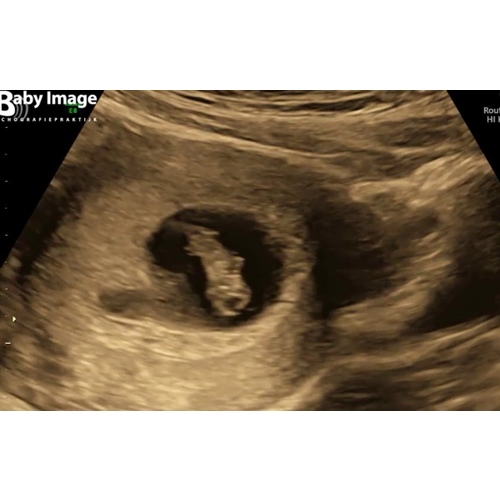

Kimberly die van mij dan? Deze was met 7 weken.uitwendige echo